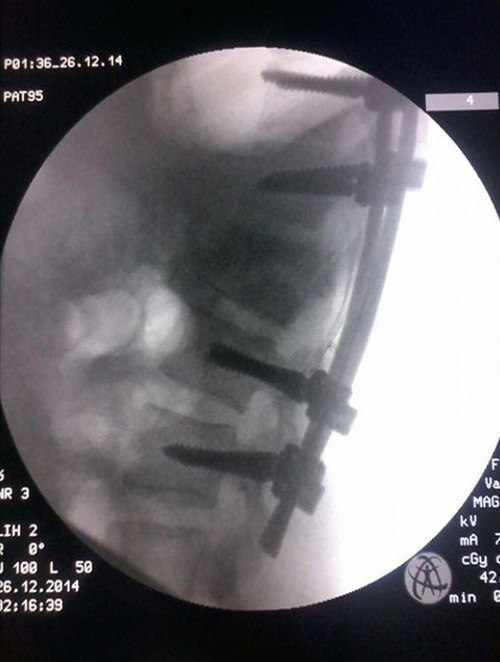

ما هي عملية تثبيت الفقرات تعتبر عملية تثبيت الفقرات واحدة من العمليات التي يحدث فيها دمج أو تثبيت للفقرات بحيث يتم تثبيت فقرة أو فقرتين مع بعضهما البعض.

تثبيت الفقرات بالبراغي تعتبر تثبيت عيادة الدكتور غزوان عبدالله حسن لجراحة العمود الفقري والمفاصل والكسور فيسبوك